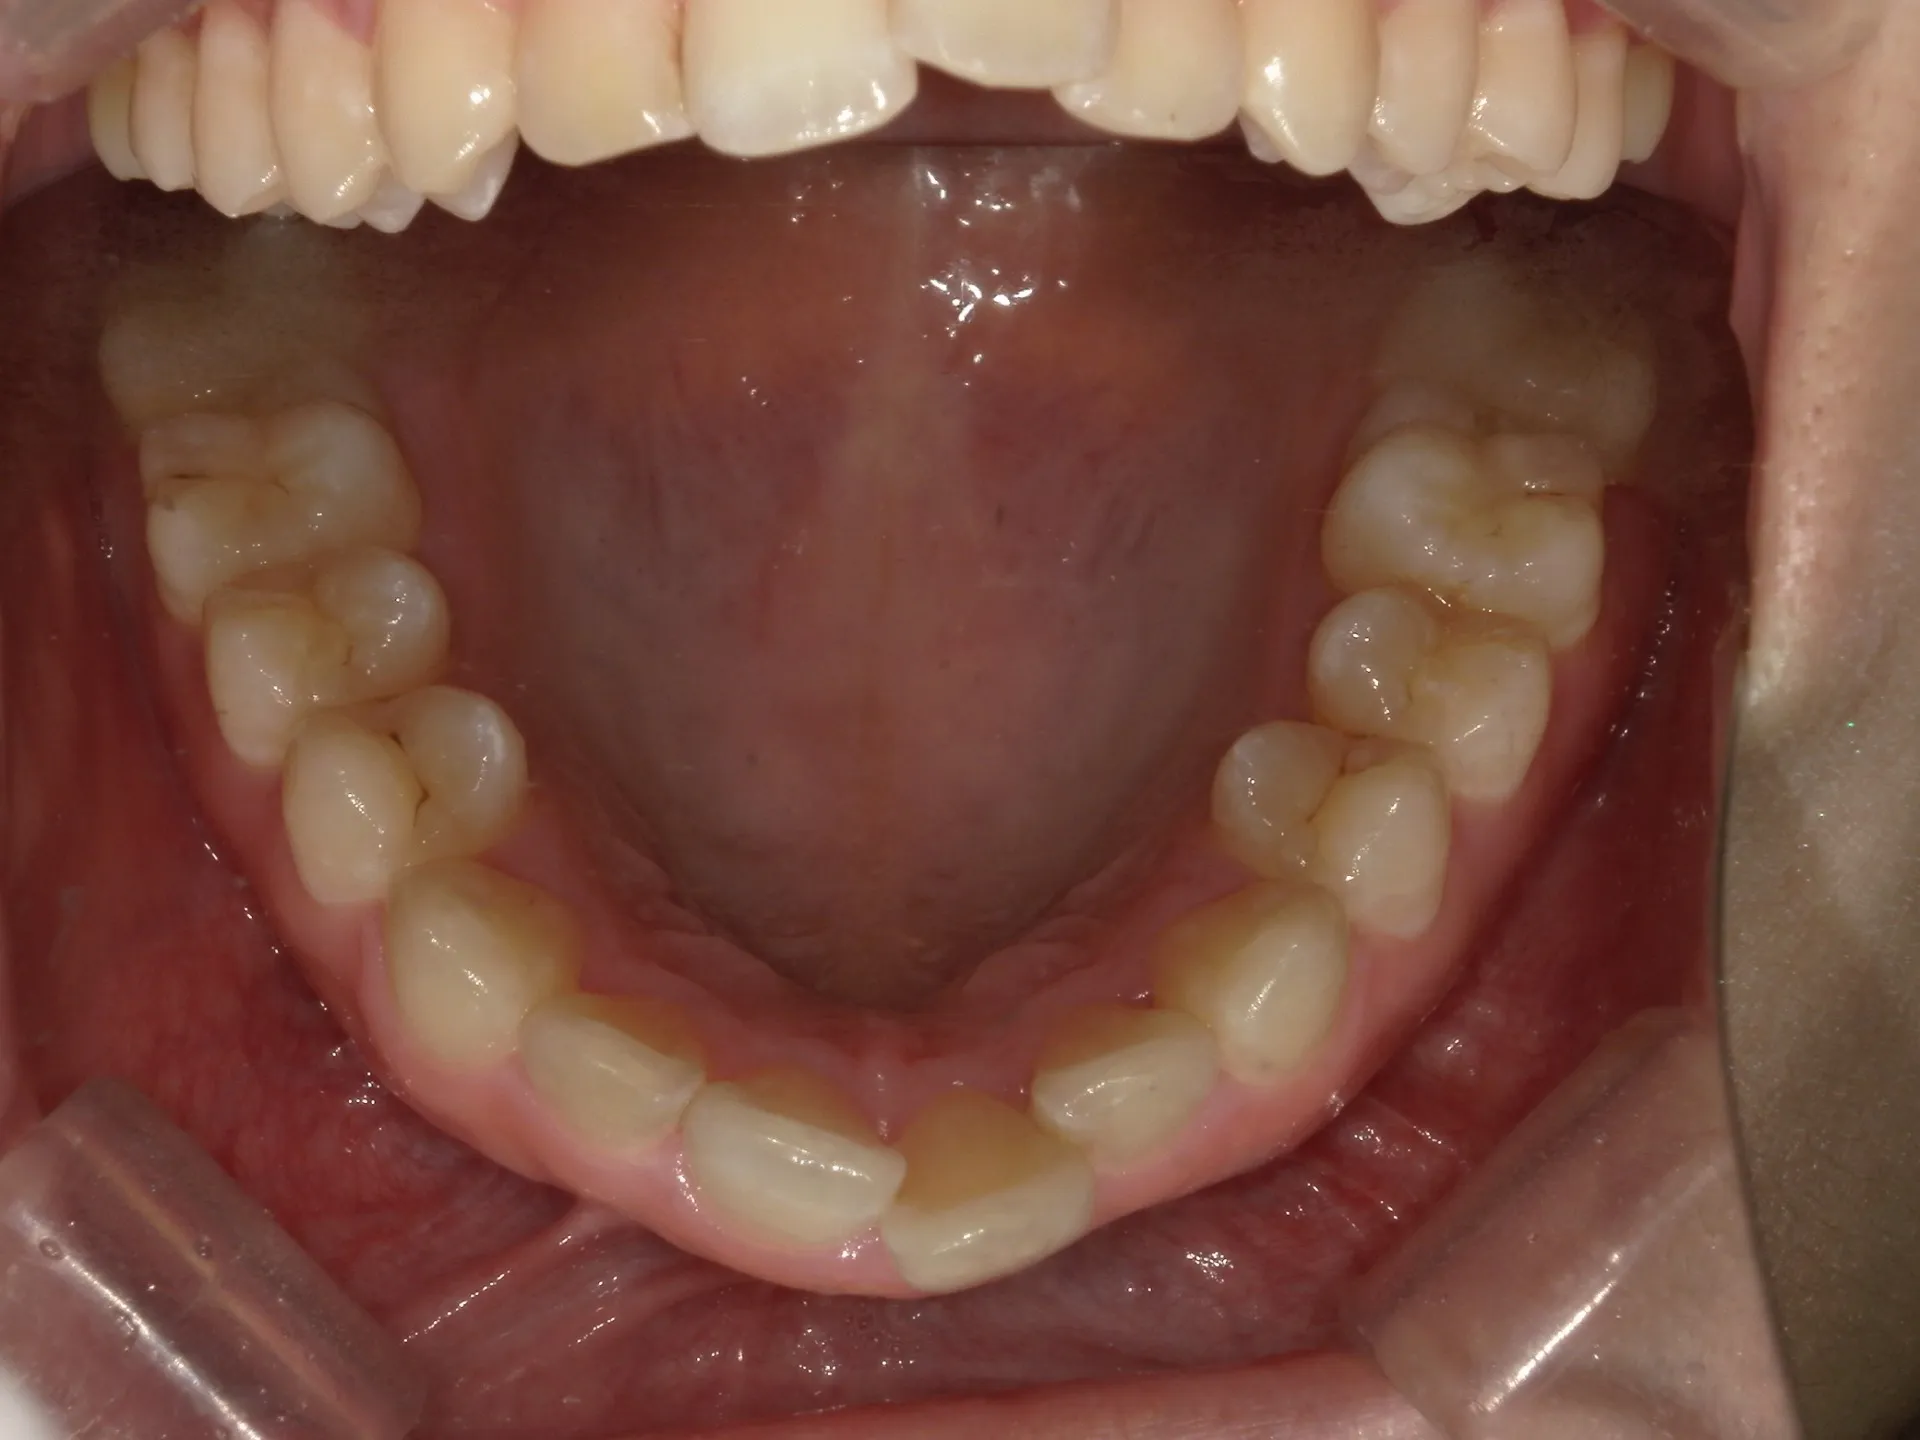

今回はマウスピース矯正(インビザライン)で前歯の出っ張りを治したケースをご紹介いたします。

マウスピース矯正で前歯の出っ歯感を抑えることが可能で、このケースでは上の歯のみ2本の抜歯を行っています。